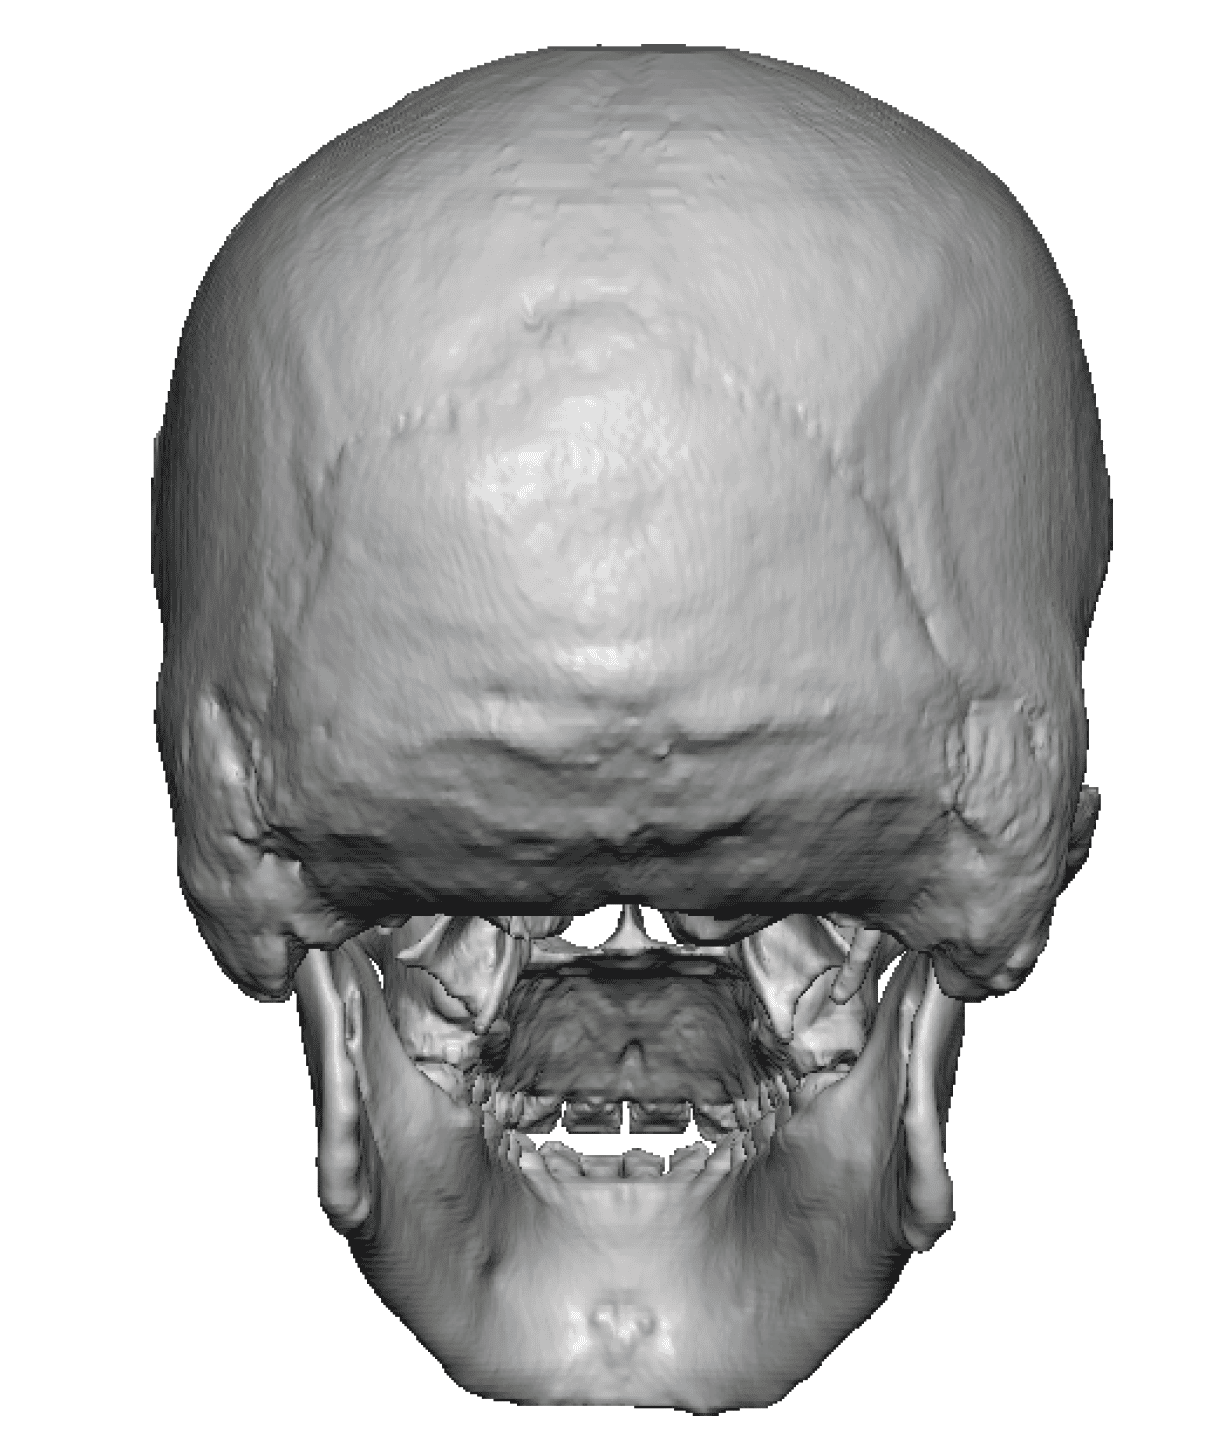

Severe narrowing skull deformity from prior sagittal craniosynostosis repair as an adult.

Complete replacement of entire skull by a custom implant with temporal fat injections.

Severe narrowing skull deformity from prior sagittal craniosynostosis repair as an adult.

Complete replacement of entire skull by a custom implant with temporal fat injections.